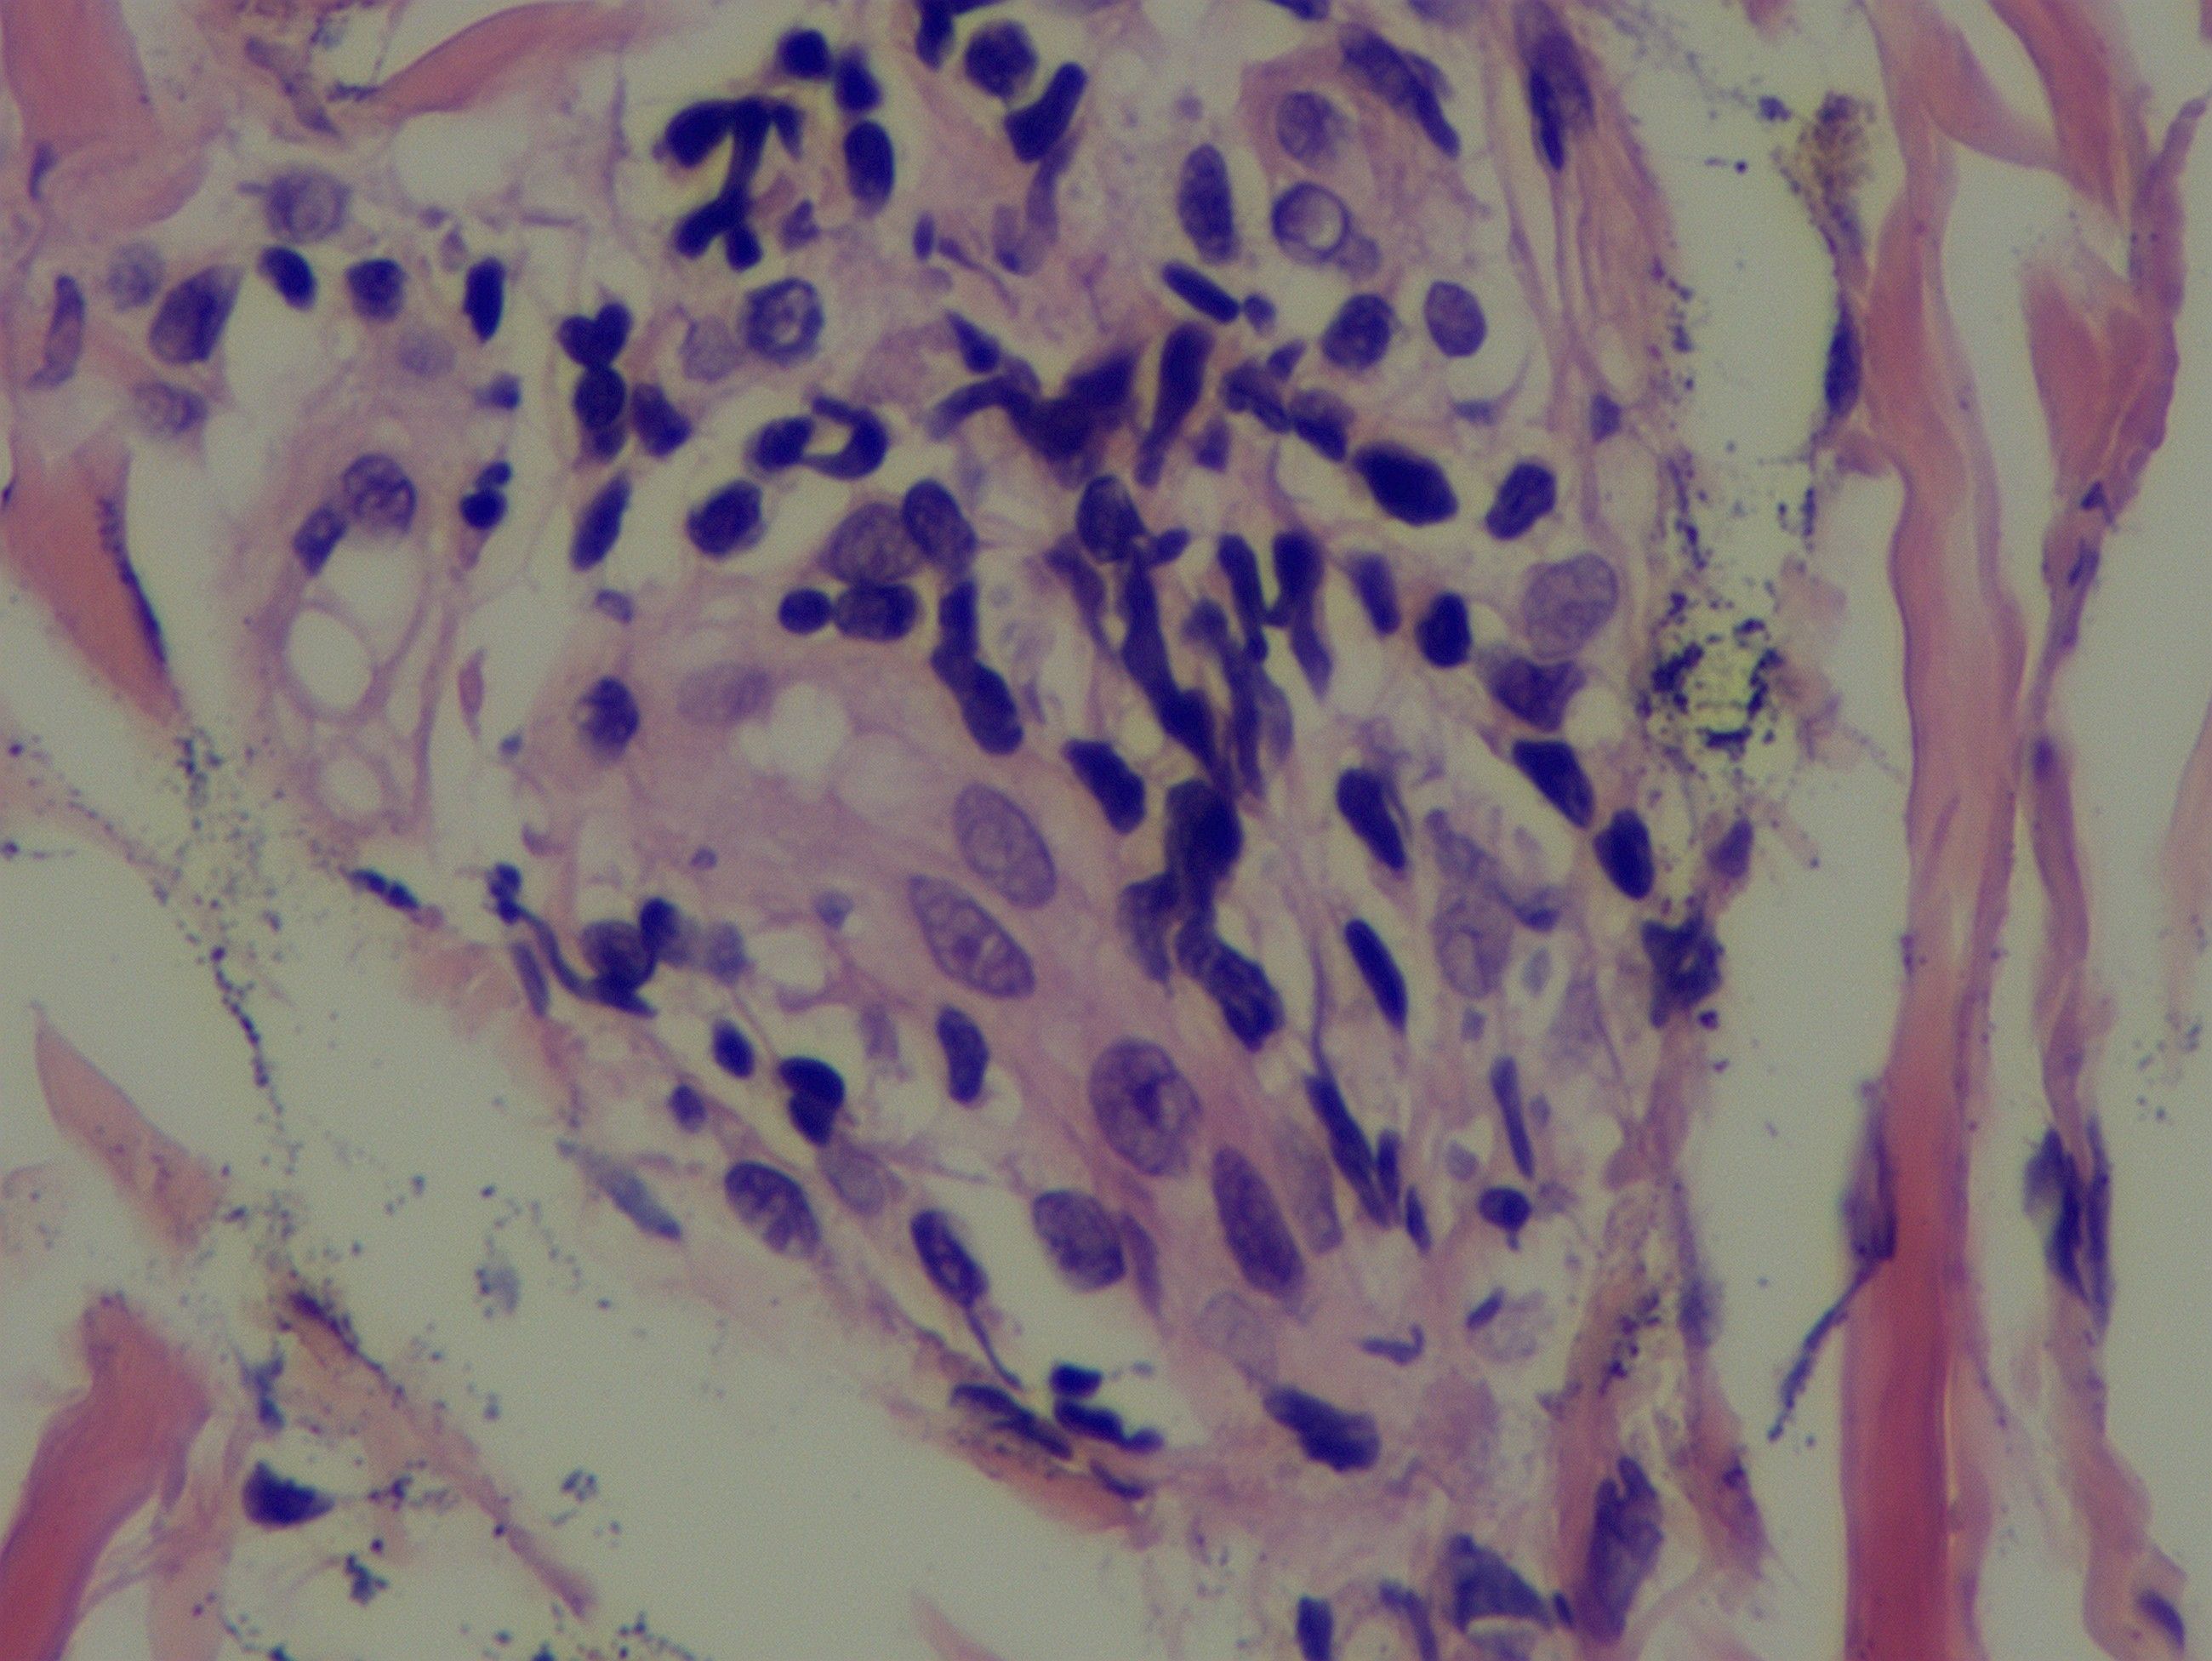

Scalp skin biopsy with hematoxylin and eosin staining showed mild epidermal hyperplasia, sparse lymphocytic infiltration around small vessels and skin appendages in the superficial dermis, predominantly T cells, and leukocytoclastic vasculitis. Immunohistochemical staining demonstrated CD3 (+), CD20 (–), CD30 (-), with approximately 10% of cells positive for KI-67, CD2 (+), CD5 (+), CD7 (+), CD4 (+), and a few CD8 (+) cells (Figure 4). The patient fulfilled the 2014 International Criteria for Behçet’s Disease (ICBD) (6), scoring 5 points derived from retinal vasculitis (2 points), recurrent oral aphthae (2 points), and folliculitis with acneiform rash (1 point), leading to the diagnosis of Behçet’s disease.

Figure 4. A scalp skin biopsy specimen indicated mild epidermal hyperplasia and a sparse lymphocytic infiltration, predominantly T lymphocytes, in the dermal superficial skin appendages and small blood vessels.